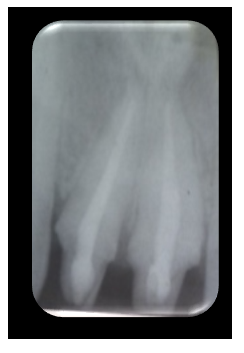

The extraoral examination revealed a dental smile. The intraoral examination showed inadequate oral hygiene, with discoloration on the lingual surfaces of the teeth due to smoking. From a periodontal perspective, there was misalignment of the gingival margins, a pseudo-pocket of approximately 4 mm in the region of tooth 11, and a significant vestibular bulge in the anterior maxillary sector, covered by mucosa of normal appearance. At the dental level, both central incisors exhibited an atypical (cuspidated) morphology and were malpositioned (rotation and version), along with anterior mandibular crowding (Figure 1).

Figure 1 Initial situation.